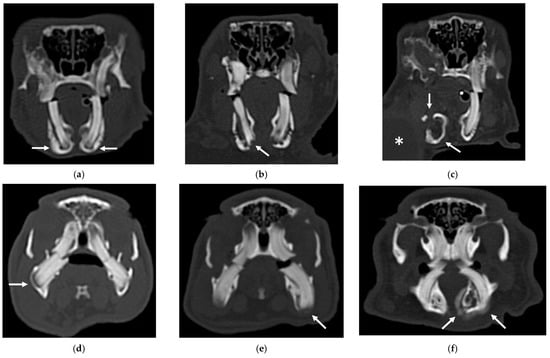

An example of the three categories of secondary bone lesions is shown for a rabbit and a guinea pig in Figure 2.

Figure 2.

Transverse CT images of mandibular secondary bone lesions of three rabbits (a–c) and three guinea pigs (d–f) included in the study; bone algorithm. (a,d) Bulging around tooth without focal lysis (white arrows); (b,e) bulging around tooth with focal lysis (white arrow); (c,f) aggressive bone lesion associated with teeth (white arrow). Note the associated cavernous occupying lesion of soft tissues (white asterisk) in image (c).

The IT were more frequently involved in guinea pigs with aggressive bone lesions associated with teeth (3). In the second group of patients, variable involvement of different groups of teeth was observed. The involvement of the premolar and molar teeth presented variable distribution in both species in all three categories of secondary bone lesions. Only three rabbits and three guinea pigs exhibited involvement of IPMT, associated with aggressive bone lesion associated with teeth (3) in rabbits, and bulging around tooth root with focal lysis (2) and aggressive bone lesion associated with teeth (3) in guinea pigs, respectively, in two and one patients.